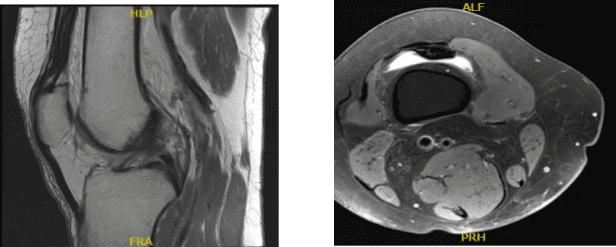

A 68 year-old female patient was seen in the office with right knee pain at Mather hospital and put in a knee brace and referred to us. MRI were reviewed and discussed by the doctor; Complex tear of the medial meniscus.

Mild MCL sprain superimposed on chronic scarring. Moderate chondromalacia patella and mild cartilage loss in the medial compartment. Moderate joint effusion.

MRI Right Knee Non-contrast

Examination of the medial tibiofemoral compartment showed a complex tear of the posterior horn of the medial meniscus along with grade 2 to grade 3 osteoarthritis of the medial femoral condyle.

Examination of the patellofemoral compartment showed grade 3 to grade 4 osteochondral lesion of the lateral facet of patella. Trochlea was intact. Debridement of the patella was done with the use of a shaver.

Intraoperative images